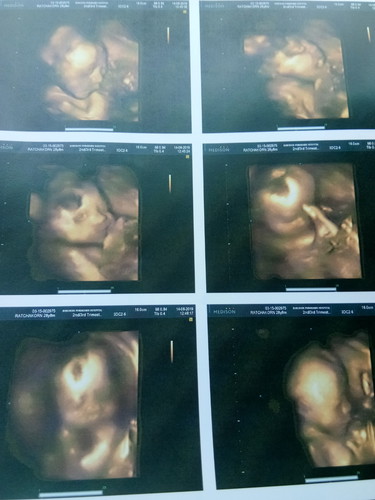

อัลตราซาวนด์4มิติ 29สัปดาห์

29สัปดาห์ เป็นโครงสร้างรูปร่างเหมือนเด็กทารกชัดมาก ให้ความร่วมมือกับคุณหมอดีมากลูก แข็งแรงปกติดีจ้า อยู่ในช่วงตื่นพอดี เลยได้หลายภาพ

บังเอิญจังหวะเต้าตื่นพอดี เป็นคนอ้วนค่ะ ตอนนี้หนัก93กก. กลัวมองไม่ชัดมาก แต่ก้เห็นชัดค่ะ โล่งไปที กลัวเสียตังค์ฟรี555

แม่บ้านนี้29สัปดาห์ 1,470กรัมค่ะ

29วีคเท่ากันเลยค่ะ น้องน้ำหนักเท่าไหร่คะคุณแม่